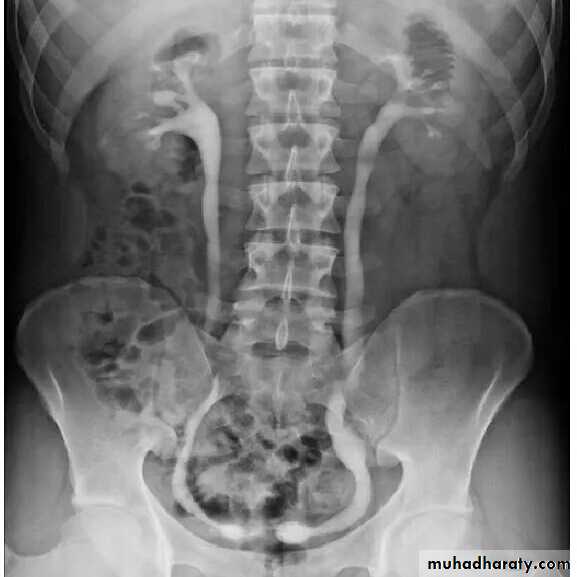

retrocaval ureter

2. Pelviureteric junction obstruction (PUJ):

peristalsis is not transmitted across thepelviureteric junction i.e. functional obstruction.

usually discovered in children and young adults.

Imaging show dilatation of all the calices and

renal pelvis with abrupt change in caliber to

a narrow or normal ureter